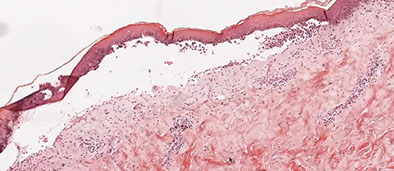

Porphyria cutanea tarda (PCT)

MCC porphyria in the states; assoc c Hep C and AIDS, EtOH, iron overload and possibly inherited deficiency of uroporphyrinogen decarboxylase (in heme synth), which are found in the liver

- get blisters in sun-exposed areas (back of hands)

Subepidermal pauci-inflammatory vesiculation; thick acral skin c compact orthokeratosis;

- Caterpillar bodies - compact hyaline material

- festooning of dermal papillae (protrude into blister)

- hyalinization of blood vessels

IHC: PAS can highlight deposition of perivascular hyaline

IF: IgM and C3 in vessels (absorbed by hyaline)

Porphyria cutanea tarda c festooning of the dermal papilla (protruding into the blister)

PCT